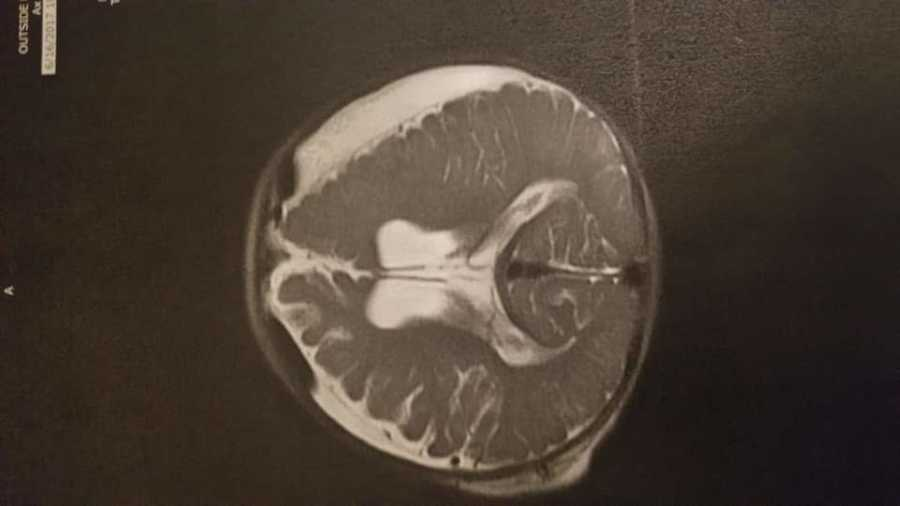

My son was born in October 2016 on a Native American booking in Montana. At first, he seemed like any other healthy baby. But when he was five months old, something went awfully wrong. He was rushed to the hospital, and the doctors found bleeding on both sides of his brain and in his eyes. Someone had dazed him. They flew him to Salt Lake City for emergency surgery, where doctors placed a shunt to help drain the blood from his brain. That push will stay in for the rest of his life.

There are still tests. He needs regular MRIs, and we have to watch him closely because of his shunt. But he’s already beaten the odds, and we believe he’ll do amazing things. We didn’t expect this path. But now, we can’t see life without him.